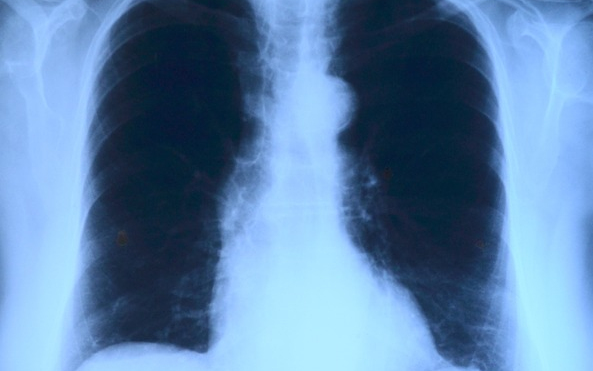

Az országban elsőként a Debreceni Egyetem Klinikai Központjában végeztek tüdőverőér-tágítást - közölte a felsőoktatási intézmény sajtóirodája kedden az MTI-vel.

A nemzetközi orvoscsoport múlt hét szombaton két betegnél hajtotta végre a beavatkozást, amellyel a tüdőerek magas vérnyomását csökkentették. Mindkét páciens krónikus thromboembóliás pulmonális hipetróniában szenvedett, amely súlyos nehézlégzést, kisebb fizikai terhelhetőséget és akár eszméletvesztést is okozhat. Az első hazai ballonos pullmonális értágítást (BPA) Irene Lang professzor, a bécsi Allgemeines Krankenhaus (AKH) kórház II. Belgyógyászat-Kardiológiai osztályának vezetője és tanítványa, Christian Gerges végezte a debreceni kardiológiai és szívsebészeti klinika intervenciós kardiológusainak közreműködésével - olvasható az egyetem közleményében.

A nagy szakértelmet és türelmet igénylő, komplex katéteres eljárást egy 59 éves férfinál és egy 82 éves nőnél végezték el. A 2-3 órás beavatkozás során a tüdő véráramlását akadályozó vérrögöket ballonnal kitágították, így az áramlási akadály mérséklődött, a tüdőerekben pedig csökkent a nyomás, ezzel együtt a szív terhelése is.

A módszert a világon először 1988-ban alkalmazták, az első nagyobb betegszámú vizsgálatot 2001-ben publikálták, 2004-től pedig elsősorban Japánban tökéletesítették az eljárást, amely azóta az Egyesült Államokban, Norvégiában, az utóbbi évtizedben pedig Európa más országaiban is egyre elterjedtebb lett.

A közleményben hangsúlyozzák: A Debreceni Egyetem szakemberei bíznak benne, hogy az eljárást Lang professzor és munkatársai, valamint a Klinikai Központ orvosai segítségével sikerül meghonosítani Magyarországon is. A betegek életében ugyanis jelentős változást hoz a BPA-beavatkozás, a kezelés következtében csökkennek a fulladásos panaszok és nő a fizikai terhelhetőség.

A módszer nagy előnye a rövid felépülési idő, hiszen a műtét utáni kétnapos intenzív megfigyelést követően a betegeket akár már a harmadik nap hazaengedhetik. Az első magyarországi ballonos tüdőverőér-tágításon átesett betegek jól vannak, kedden már el is hagyhatták a klinikát - zárul az egyetem közleménye.